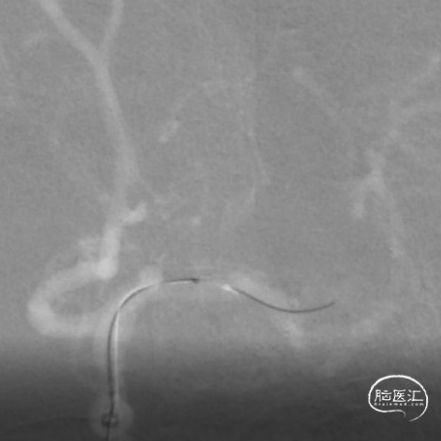

使用Tethys®中间导引导管+DCwire®微导丝通过右侧大脑中动脉M2段闭塞病变处。

微导管造影提示位于血管真腔,3*15mm 支架打开后前向血流未恢复,考虑存在动脉瘤,支架取栓操作有风险,故交换支架予以1.5*15mm 球囊扩张。